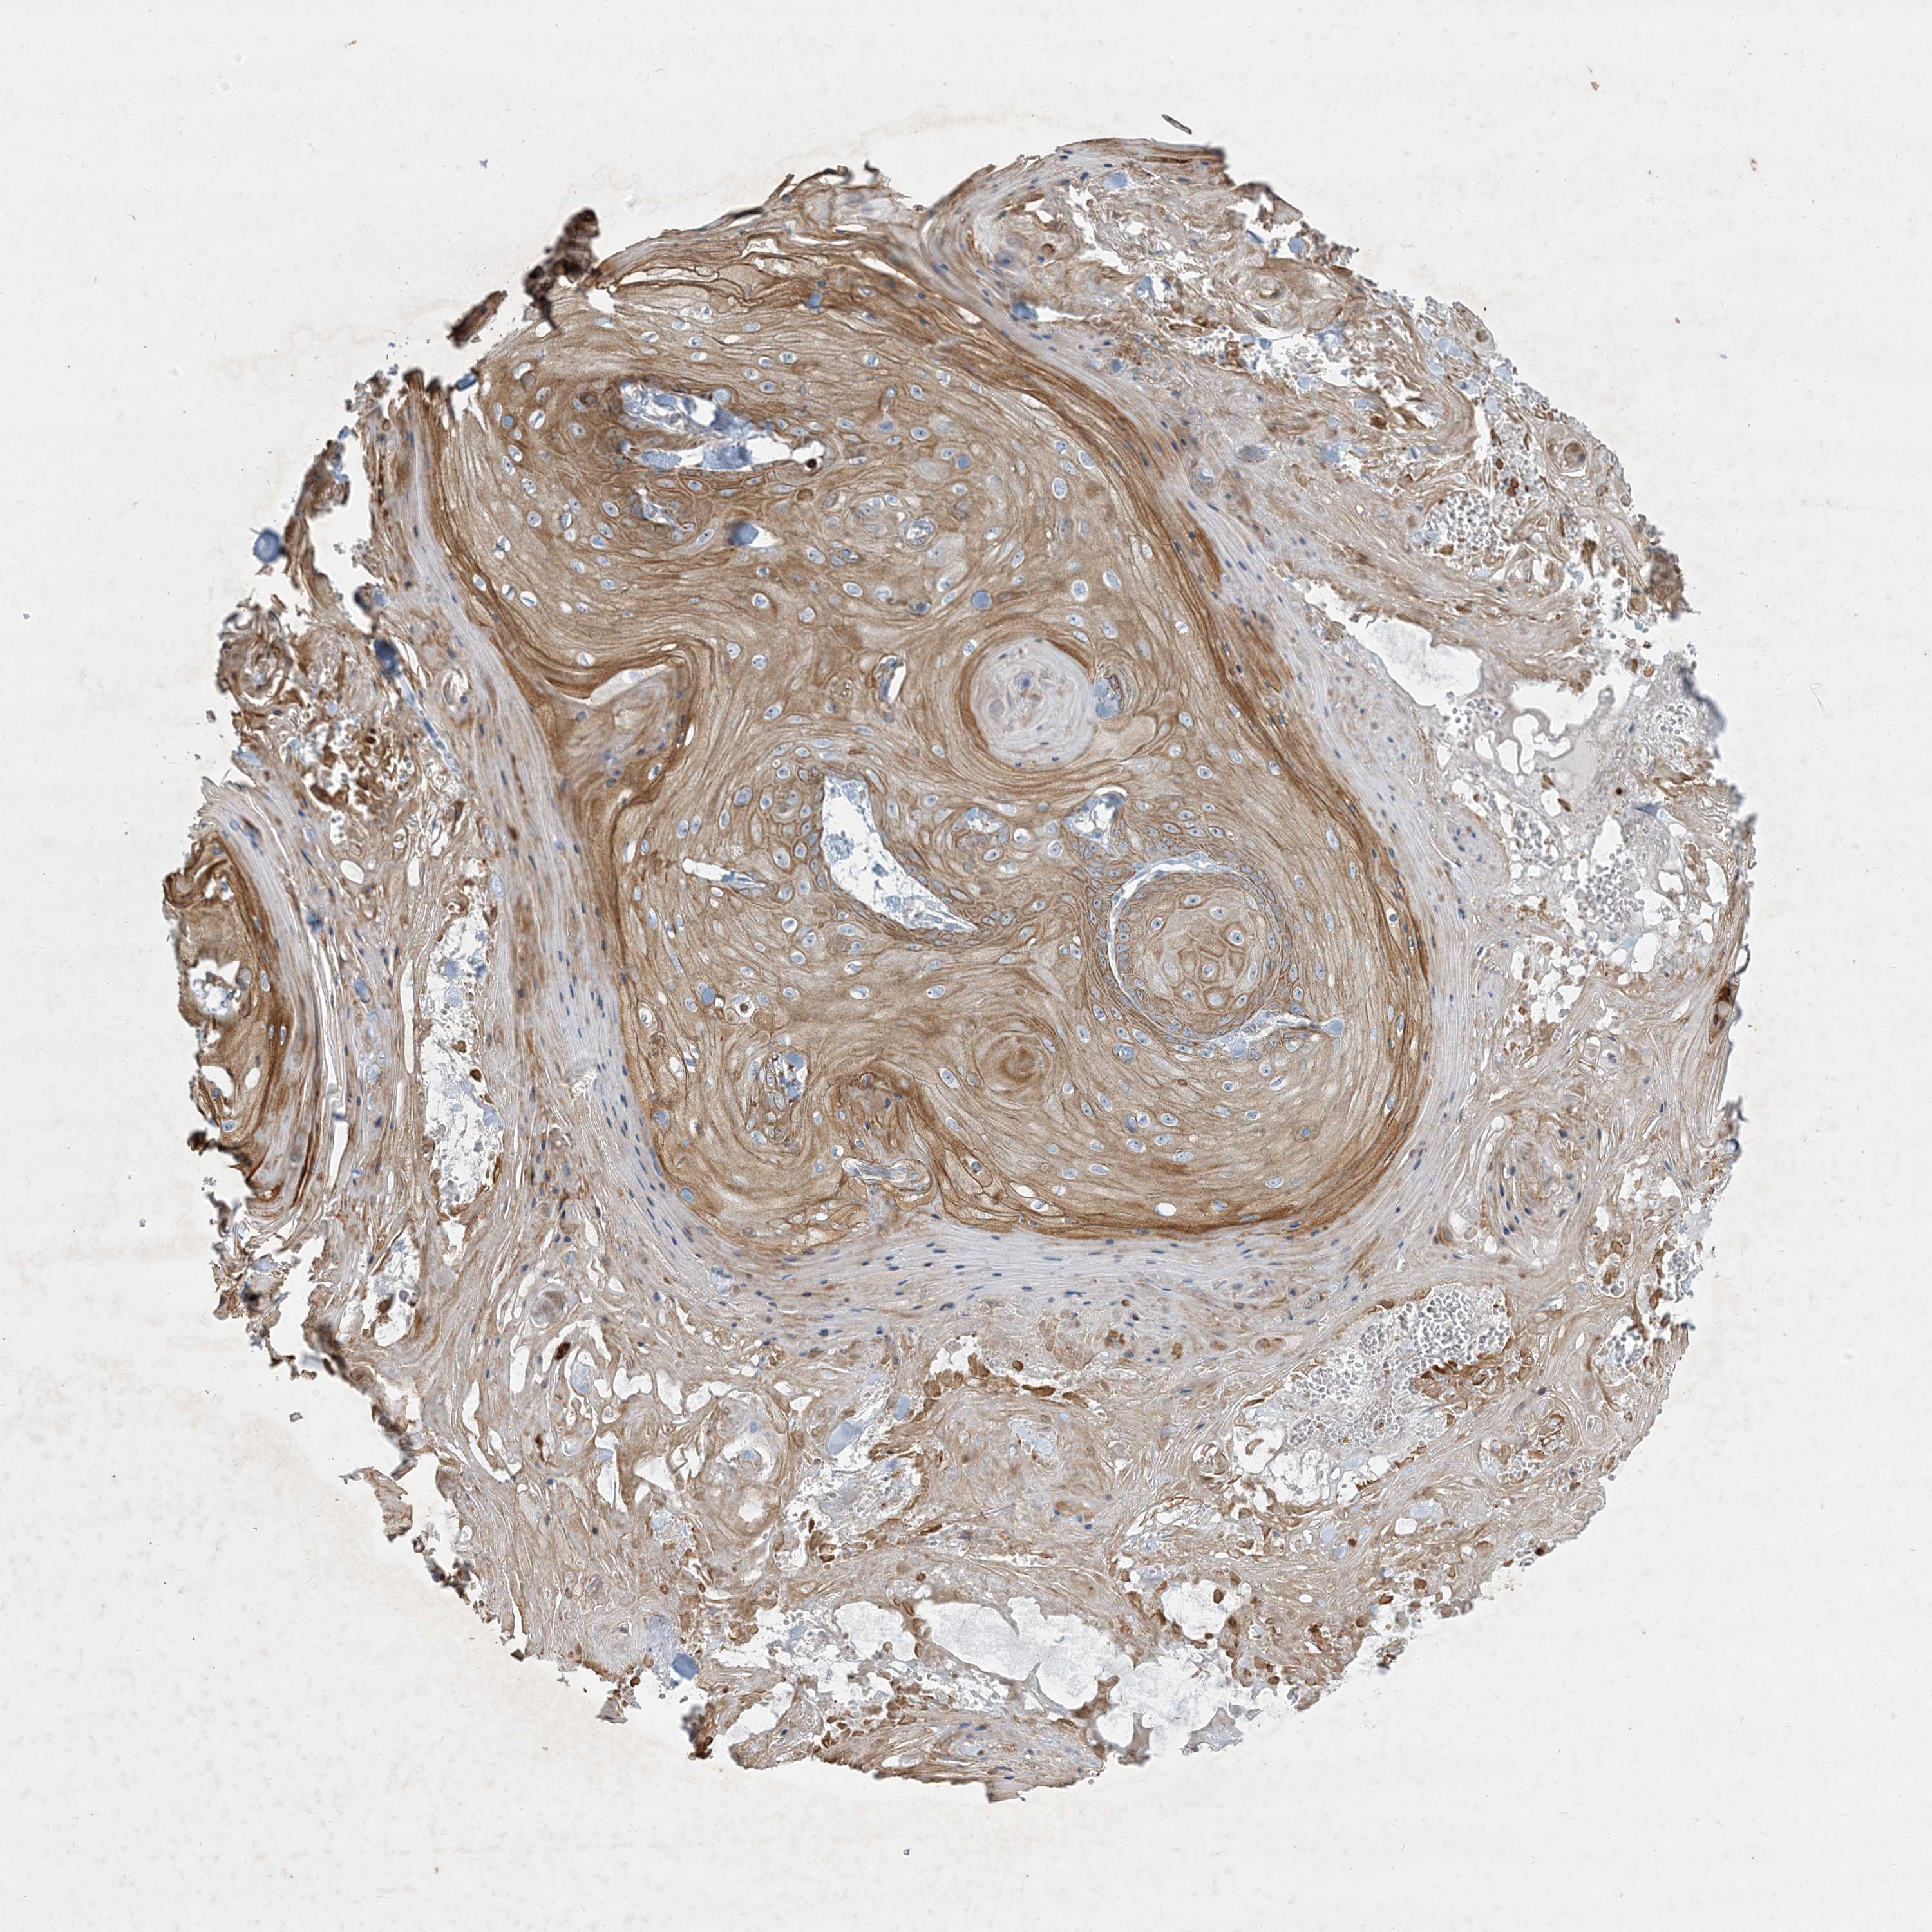

Basal cell and squamous cell cancer

SKIN CANCER - Protein expressioni

A mouse-over function shows sample information and annotation data. Click on an image to view it in a full screen mode. Samples can be filtered based on level of antibody staining by selecting one or several of the following categories: high, medium, low and not detected. The assay and annotation is described here.

Each image is clickable and will lead to virtual microscopy that enables deeper exploration of all samples and also displays staining intensity scores, fraction scores and subcellular localization as well as patient and tissue information for each sample.

Antibody HPA029143

Basal cell carcinoma